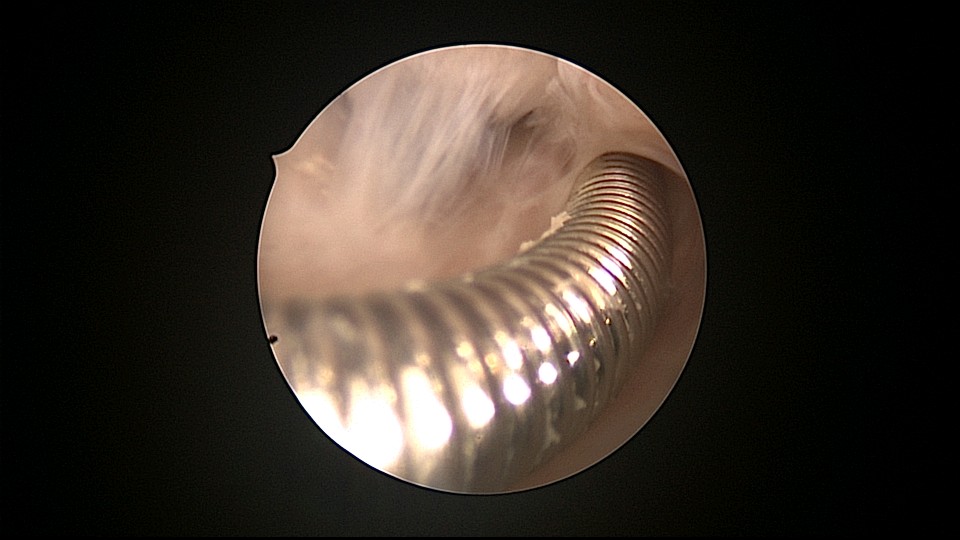

患者81岁,G5P5,顺产5次,安环50年,绝经23年,高血压病史多年,10年前因颅内肿瘤行开颅手术,4年前行腹腔镜胆囊切除术,外院介绍到我院宫腔镜取环。子宫前位,宫颈萎缩,穹隆展平,宫颈外口位于穹隆偏左侧,平滑狭小,夹持宫颈很困难,阴道内镜方式进入宫腔,见宫腔下部O型环圈内前后壁粘连,顿性分离粘连,宫腔中上部O型环与两侧宫壁嵌顿,异物钳松动节育环,但难以取出,取环钩沿镜鞘外侧进入宫腔,配合中弯钳牵拉出节育环,环变形,检查环完整,宫腔无其他异常。